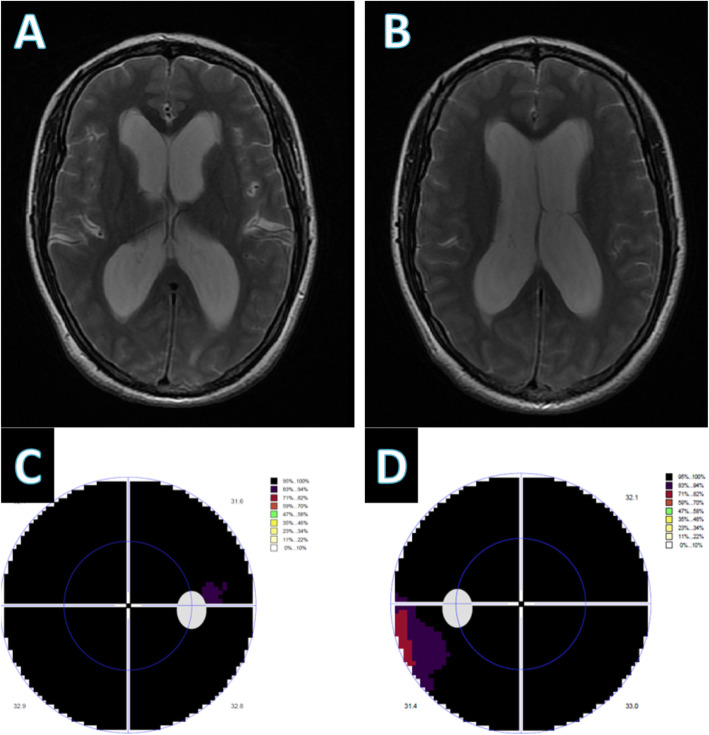

From pmc.ncbi.nlm.nih.gov

Frontotemporal brain sagging syndrome Craniospinal hypovolemia What Level Is Lumbar Puncture Done  A lumbar puncture (lp) or spinal tap may be done to diagnose or treat a condition. Opening pressure is measured with a manometer; In lumbar puncture (lp), a needle is inserted into the lumbar subarachnoid space to collect cerebrospinal fluid (csf) for laboratory testing, to measure csf pressure, and sometimes. A lumbar puncture (lp), which is also called a spinal. What Level Is Lumbar Puncture Done.